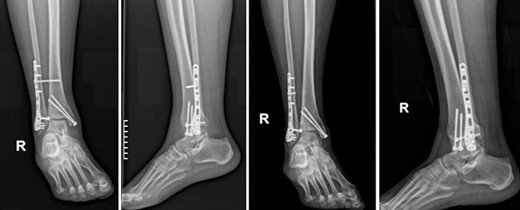

Four doses of i.v. cefoxitin (2000 mg 5 minutes prior to skin incision in the operating room and 1000 mg three times postoperatively every 8 h) were administrated as chemoprophylaxis. The postoperative period was well-progressed, and the patient was discharged on the second postoperative day with a cast and instructions against weight-bearing. In the seventh postoperative week, the patient deviated from the prescribed postoperative regimen by prematurely initiating weight-bearing activities, contrary to the surgeon’s explicit recommendations. During the regular 8-week follow-up, we observed after the radiological evaluation that the syndesmotic screw was broken. This necessitated us to remove the screw and replace it with a 3.5-mm cortical screw (Fig. 3).

Anteroposterior and lateral X-ray of the ankle joint showing the broken syndesmotic screw and the replacement with a 3.5-mm cortical screw on the lateral malleolus 8 weeks after the initial surgery.